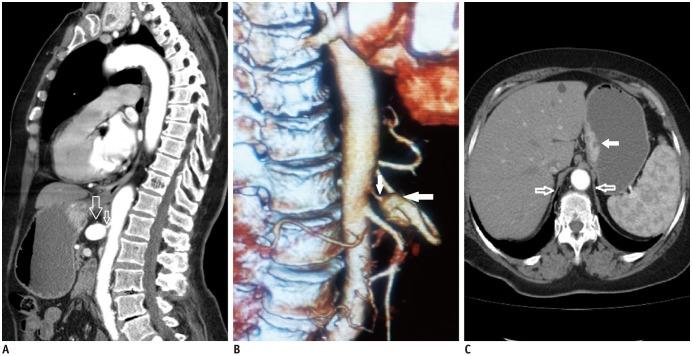

Median arcuate ligament syndrome is an anatomic and clinical entity characterized by dynamic compression of the proximal celiac artery by the median arcuate ligament, which leads to postprandial epigastric pain, vomiting, and weight loss. These symptoms are usually nonspecific and are easily misdiagnosed as functional dyspepsia, peptic ulcer disease, or gastropathy. In this report, we presented a 72-year-old male patient with celiac artery compression syndrome causing recurrent abdominal pain associated with gastric ulcer and iron deficiency anemia. This association is relatively uncommon and therefore not well determined. In addition, we reported the CT angiography findings and three-dimensional reconstructions of this rare case.